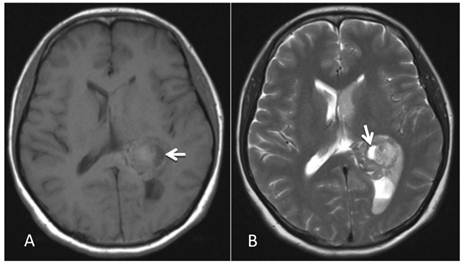

A 46-year-old female was admitted to the hospital due to a sudden onset of headache that had lasted for 5 hours. Physical examination showed neck stiffness and Kernig's sign but no other positive signs of the nervous system. Computed tomography (CT) showed a high-density space-occupying lesion in the trigone of the left lateral ventricle. Hemorrhage surrounded the lesion and formed a hematoma, which extended forward into the contralateral ventricle and affected the third and fourth ventricles (Figure 1). Computed tomography angiography (CTA) showed no intracranial artery malformation. The medial blood vessels of the lesion in the trigone of the lateral ventricle were disordered, and the lesion was supplied by anterior and posterior choroidal arteries. Maximum intensity projection clearly revealed a high-density calcification shadow at the rear of the lesion, and the surrounding brain tissues were mildly compressed (Figure 2). Magnetic resonance imaging (MRI) showed that the area of the lesion was 2.86 cm × 2.68 cm with mixed T1WI and T2WI signals. The lesion was heterogeneous in density, and its center was cystic. Slightly high abnormal T1WI and T2WI signals were noted in the bilateral lateral ventricles, and fluid was visible in the occipital horn of the left lateral ventricle (Figure 3).

Figure 3

MRI examination. A-B: A 2.86 cm × 2.68 cm space-occupying lesion was detected in the trigone of the left lateral ventricle; T1WI and T2WI showed mixed signals, and a cystic shadow was noted within the lesion. Slightly high abnormal T1WI and T2WI signals in the bilateral lateral ventricles were observed, and fluid was visible in the occipital horn of the left lateral ventricle (arrow).